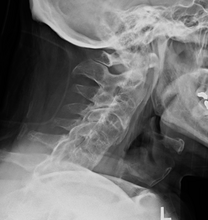

In severe cases of AS, surgery can be an option in the form of joint replacements, particularly in the knees and hips. Surgical correction is also possible for those with severe flexion deformities (severe downward curvature) of the spine, particularly in the neck, although this procedure is considered very risky.

In addition, AS can have some manifestations which make anesthesia more complex. Changes in the upper airway can lead to difficulties in intubating the airway, spinal and epidural anesthesia may be difficult owing to calcification of ligaments, and a small number of people have aortic insufficiency. The stiffness of the thoracic ribs results in ventilation being mainly diaphragm-driven, so there may also be a decrease in pulmonary function.